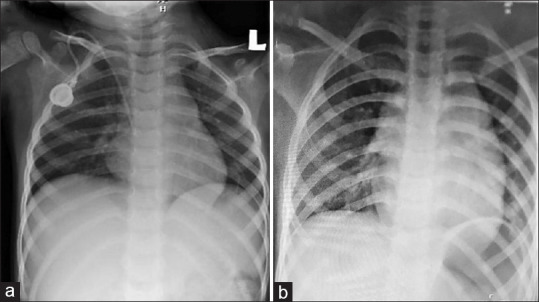

Abstract: A chemoport is widely used in paediatric oncology population. Removal is a relatively easy procedure, but difficulty can be encountered in case the catheter is densely adherent to the vascular wall. It is a rare complication and is associated with long indwelling duration and acute lymphoblastic leukaemia (ALL). Forceful traction can lead to vascular injury and high morbidity. Herein, we report a 7-year-old girl with precursor B ALL who had delayed chemoport removal due to the coronavirus disease (COVID-19) pandemic. The removal process was difficult, as the catheter was adherent to the right innominate vein. Out of panic, the surgeon pulled it out forcefully. Fortunately, the catheter and its fragment were successfully retrieved completely and the child was discharged the next day. The management strategy varies and ranges from minimally invasive to open surgery. Leaving a stuck chemoport catheter in situ can be a bailout method or part of conservative management.